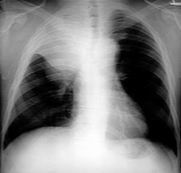

Pleural Effusion

Can see 25 mL on lat decub

Can see 300 mL on PA

Loss of costophrenic angle

Loss of diaphragmatic shadow

Homogenous opacification

Shift of mediastinum to opposite side

Ellis line

Etiology (common diseases)

Congestive heart failure

Cancer

Tuberculosis

Empyema

Hemothorax